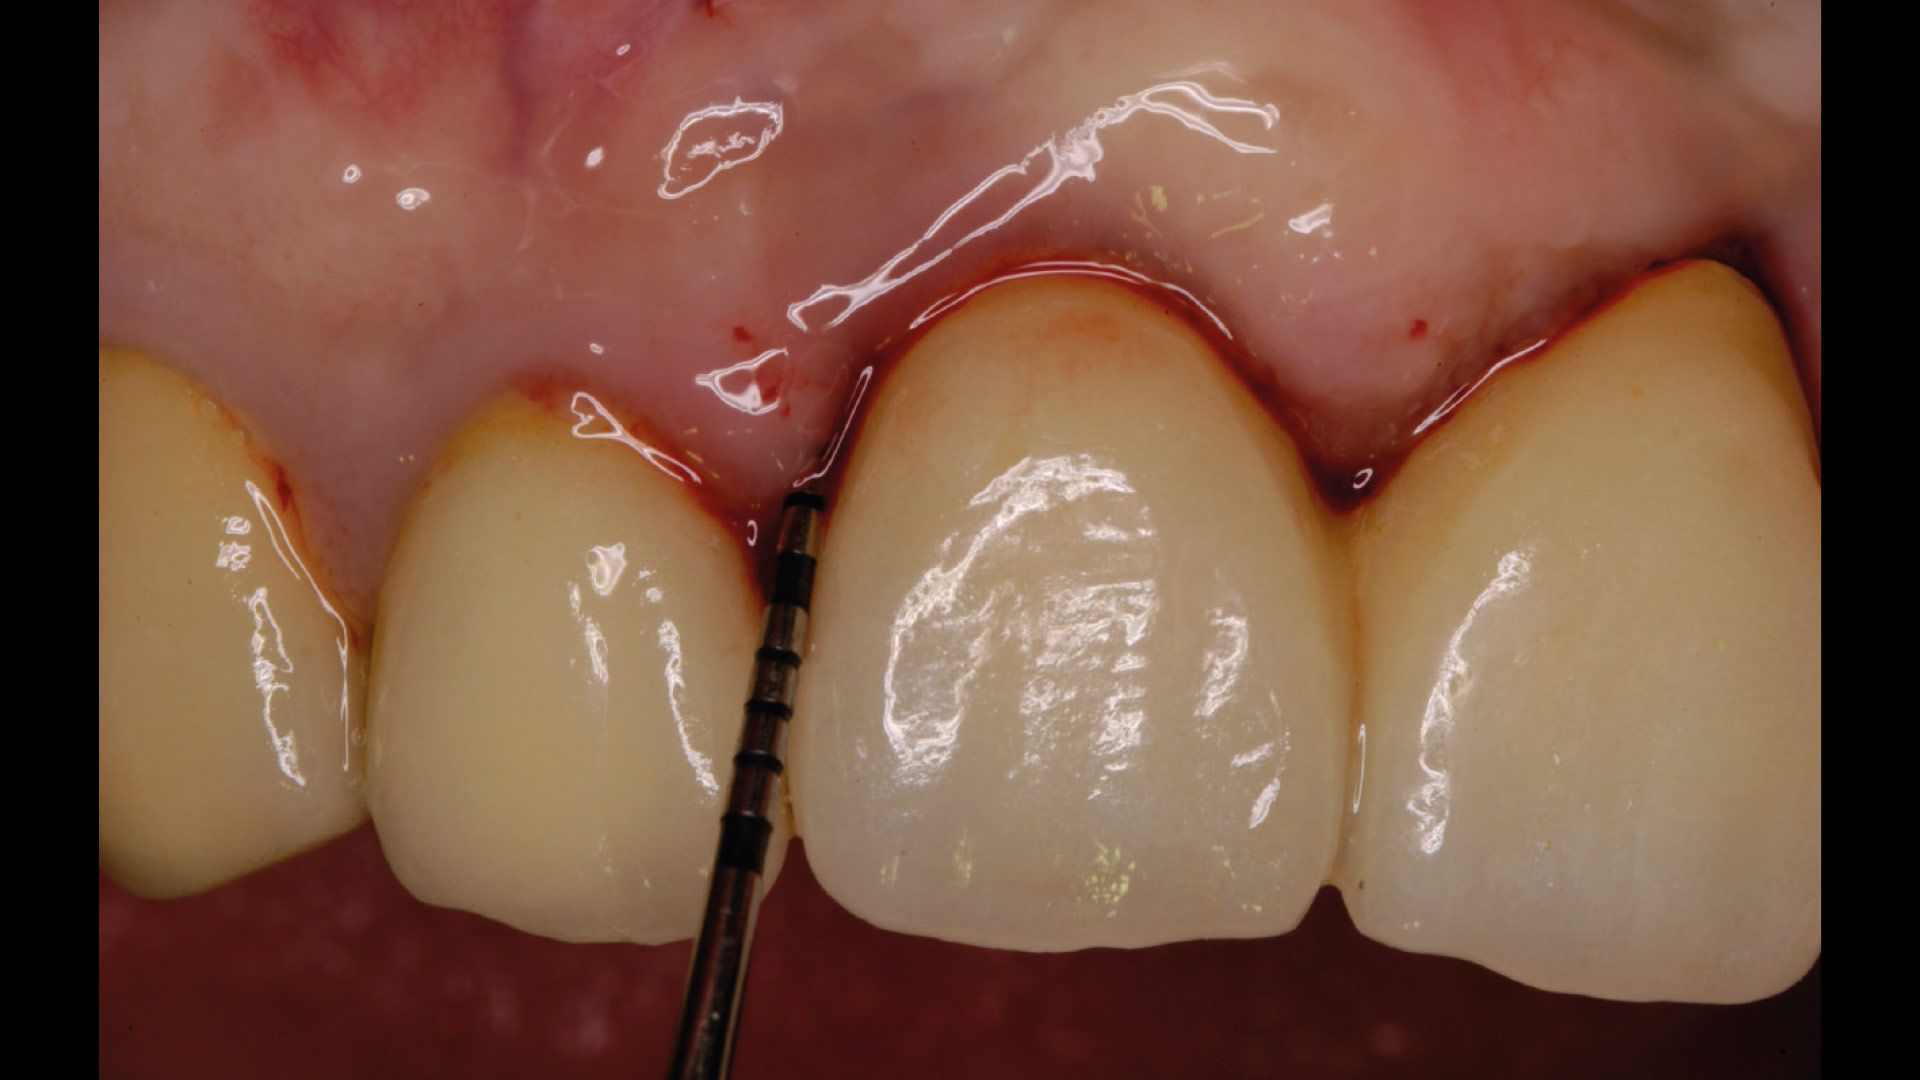

Lo studio è stato condotto presso studi dentistici privati con sede a Roma e Como. Sono stati reclutati 27 pazienti e divisi in gruppo 1 (applicazione di gel a base di clorexidina nei siti con mucosite perimplantare), gruppo 2 (applicazione di gel a base di Ozono) e gruppo 3 controllo (senza utilizzo di gel topici). Al baseline (T0) si è proceduto a valutare lo stato clinico dell’elemento implantare attraverso foto e radiografie periapicali, è stato poi rilevato l’indice di sanguinamento (Gengival Index) e successivamente è stato eseguito un debridement sub-gengivale tramite l’utilizzo di Glicina. Per il trattamento domiciliare ai pazienti sono stati consegnati gel a base di Ozono o di Clorexidina al 1% da applicare nei siti tramite lo scovolino. A T1(a 1 mese da T0) e a T2 (a 3 mesi da T0) sono state ripetute le stesse valutazioni e le stesse manovre professionali (Figg. 1a-6).

Nei pazienti afferenti al primo gruppo tra T0 e T1 si è osservato una significativa riduzione del sanguinamento al sondaggio, peggiorato poi in T2 successivamente all’interruzione dell’applicazione del gel. Nel secondo gruppo si è avuta una costante riduzione del sanguinamento al sondaggio tra T0 e T1, continuata anche in T2. In fine nel gruppo controllo il sanguinamento al sondaggio tra T0 e T1 è risultato essere incostante, così come in T2 dove non sempre vi è stato un miglioramento dell’indice di sanguinamento.

Figg. 1a, 1b - Gruppo 1: elemento 46, immagine acquisita a T0; Fig. 2 - Gruppo 1: elemento 46, immagine acquisita a T1; Fig. 3 - Gruppo 1: elemento 46, immagine acquisita a T2; Figg. 4a, 4b - Gruppo 2: elemento 11, immagine acquisita in T0; Fig. 5 - Gruppo 1: elemento 11, immagine acquisita in T1; Fig. 6 - Gruppo 2: elemento 11, immagine acquisita in T2.